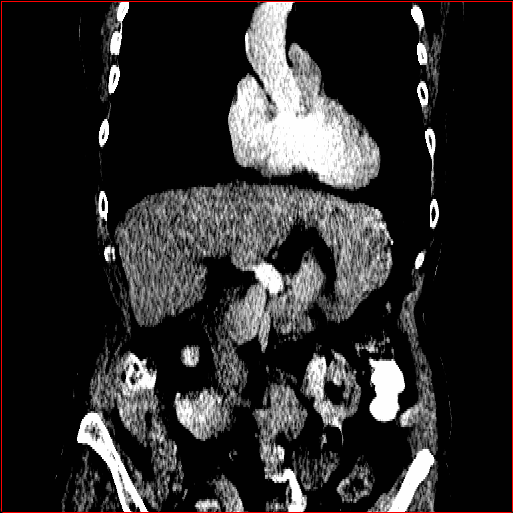

Figure 2: Qualitative comparison across axial (top row), sagittal (middle row), and coronal (bottom row) views. Columns correspond to different methods. MAISI-DDPM and MAISI-v2 in this figure are unconditional synthesis which do not use ControlNet or segmentation maps.

Qualitative Evaluation:

Figure 2 presents representative slices from the axial, sagittal, and coronal planes. GenerateCT (Hamamci et al. 2024) is a 2D model, so it lacks inter-slice consistency, leading to poor image quality in the sagittal and coronal views. MedSyn (Xu et al. 2024) produces noticeably blurry results with mosaic-like artifacts, such as region inside the red box. HA-GAN (Sun et al. 2022) generates visually sharp images but with mosaic-like artifacts, such as region inside the red box. Also, its voxel spacing is not available, which limits its applicability in real-world medical imaging tasks. Moreover, all three methods are restricted to synthesizing small anatomical regions. In contrast, both MAISI and MAISI-v2 are capable of generating high-quality 3D volumes that span larger body regions while preserving fine anatomical details and realistic structure.